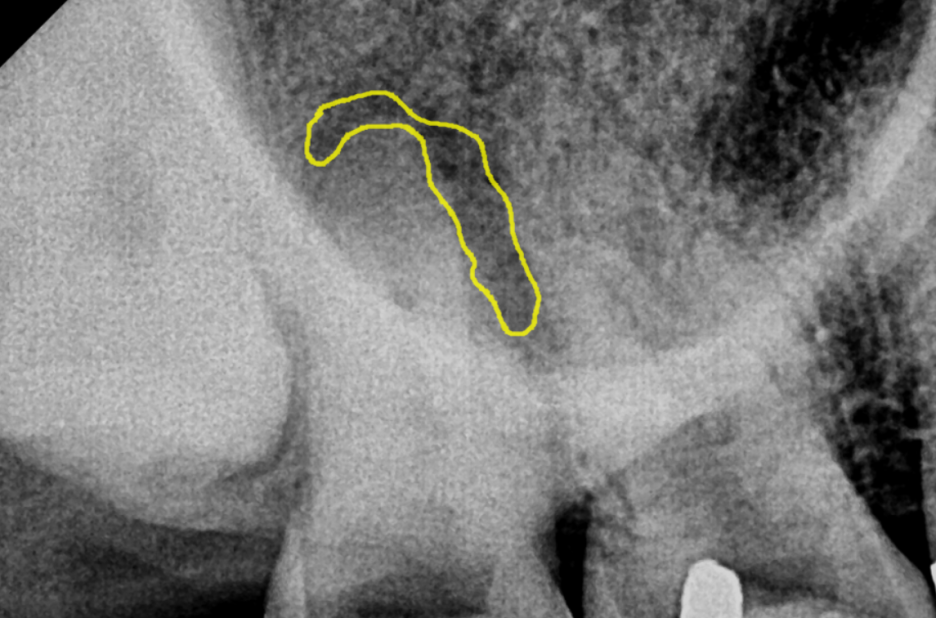

특히 이처럼 뿌리 사이(치근 분지부)에 있는 염증은

접근이 어려워 제거가 매우 힘듭니다.

250121

하지만 포기하지 않고 복잡한 신경관들을

꼼꼼히 제거하고 소독하는 과정을 여러 차례 반복했습니다.

염증이 어느 정도 가라앉은 후

MTA라는 재료를 사용하여 뿌리 끝을 단단히 막아줍니다.

MTA란? 높은 생체 적합성을 가진 재료로,

뿌리 끝 염증의 치유를 촉진하고 손상한 뿌리의 회복을 돕는 데

매우 효과적입니다.

*MTA 적용 사례

사진이 뚜렷하게 잘 나온 다른 환자분 사진을 예시로 보여드리겠습니다.

뿌리 끝 염증 상태 (전)

치아 뿌리 염증 빼야 된다는 치아, 이렇게 살렸습니다. 치료 방법

아쉽게도 mta치료는 건강보험이 적용되지 않습니다.

하지만 실제 적용 사례들에서

뿌리 끝 염증 치유에 도움이 되어

필요한 경우 적절하게 사용하면 치료 결과를 높일 수 있습니다.